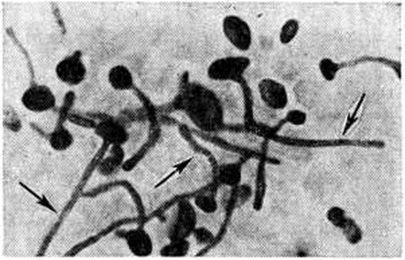

Гистологический картина изменений в метастатических очагах различных органов и тканей не имеет строго выраженных специфических черт. В начальной стадии кандидозного процесса наблюдается некротически-экссудативная воспалительная реакция, чаще гнойного характера, реже с преобладанием в инфильтрате лимфоцитов. Интенсивность разрастания грибка зависит от жизнеспособности ткани: там, где некроз выражен резче, нитей грибка значительно больше. При хронический течении процесса вокруг некротически-экссудативного очага воспаления происходит разрастание соединительной ткани или наблюдается формирование гранулемы (смотри полный свод знаний), напоминающей таковую при туберкулёзе (рисунок 3). Ликвидация грибка в организме происходит в основном за счёт лизосомальных ферментов сегментоядерных лейкоцитов (рисунок 4), то есть в результате так называемый внеклеточного фагоцитоза, поэтому рост грибка в гнойном очаге обычно тормозится. Присутствие большого количества сегментоядерных лейкоцитов препятствует размножению грибка, лейкоциты как бы облепляют элементы грибка и, подвергаясь распаду, отграничивают его от окружающей ткани (рисунок 5). Как показывают электронно-микроскопические исследования, в клетках грибка нарушается целостность цитоплазматической мембраны и появляются аутофагические вакуоли в цитоплазме. Фагоцитоз грибков сегментоядерными лейкоцитами встречается редко и касается в основном нежизнеспособных клеток грибков; в цитоплазме же макрофагов (рисунок 6) и гигантских клеток грибок может находиться длительное время и быть жизнеспособным — так называемый эндоцитобиоз. Поскольку грибок способен к внутриклеточному паразитированию, то наличие его жизнеспособных форм свидетельствует о том, что воспалительный процесс имеет затяжной характер.

Рис. 4. | ||

Рис. 6. | ||